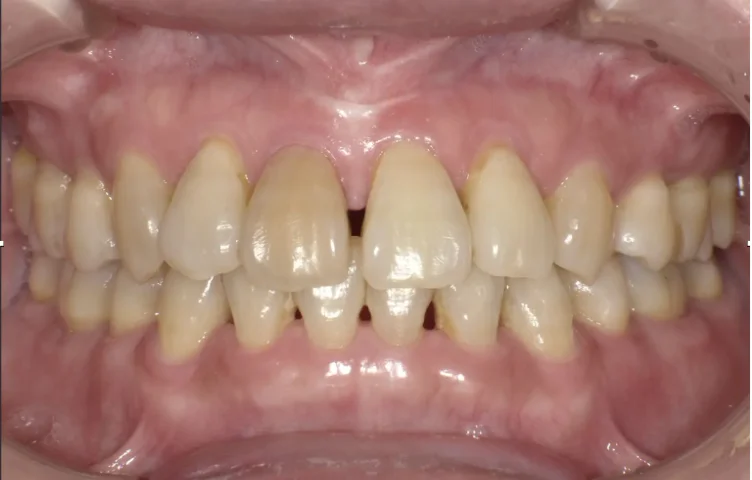

Before

After

セラミック治療により見た目と歯茎の炎症を改善(40代女性)

5回 / 総額115,000円リスク・副作用:歯軋りが強い場合破損する場合がある 歯の神経が生きている場合一時的にしみることがある